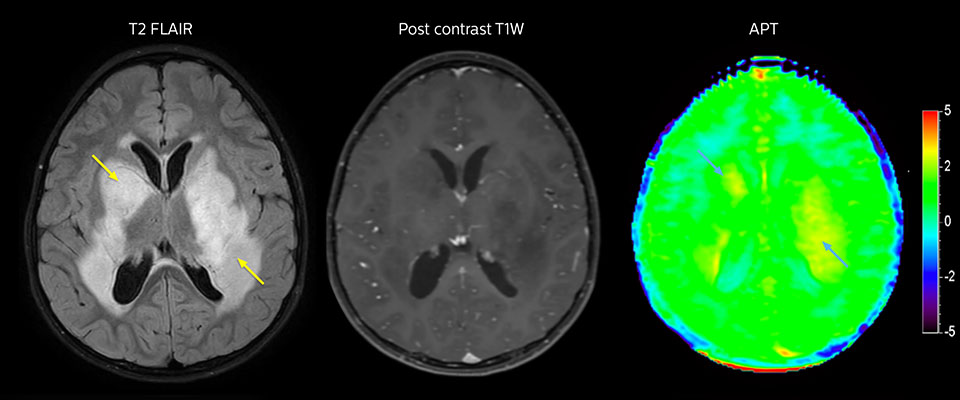

APT imaging of low-grade tumor

Low-grade glioma in a 5-year-old patient with neurofibromatosis 1. This low-grade lesion does not enhance on the post-contrast images, but does show an intermediate APT signal. The lesion stability over time confirms that it is a low-grade pathology.

Follow-up over time

Follow up results